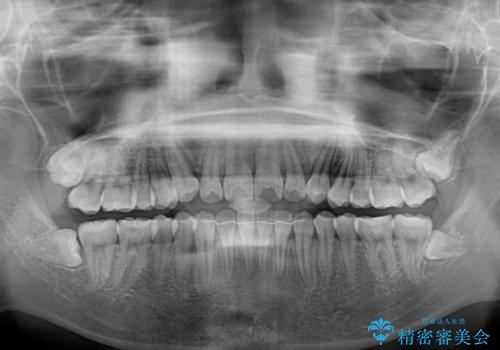

カリエールディスタライザーを併用したことで、左側臼歯の咬み合わせを確実に改善させることができました。